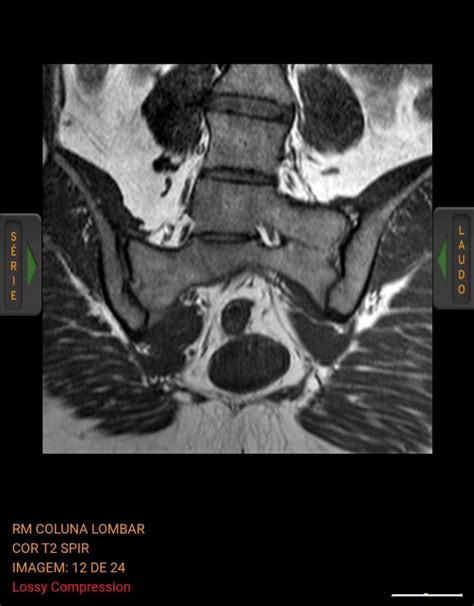

Diagnosing Lumbosacral Transitional Vertebrae

Diagnosing LSTV typically involves a combination of imaging techniques and clinical evaluation. The most common methods include:

• MRI Scans: Provide information about the soft tissues and can help assess the impact of LSTV on the spinal cord and nerves.

• lumbosacral transitional vertebrae mri